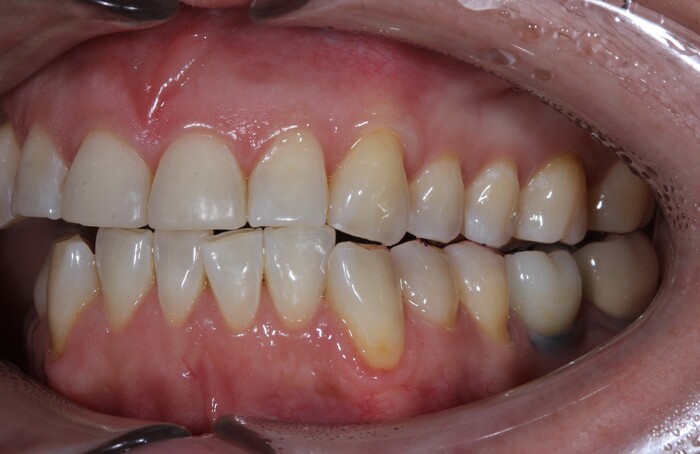

Прикус:

За эти годы ситуация усугубилась, стираемость зубов прогрессировала.

Вот как выглядели зубы в 2018 году:

А это через каких-то 3 года, 2021: